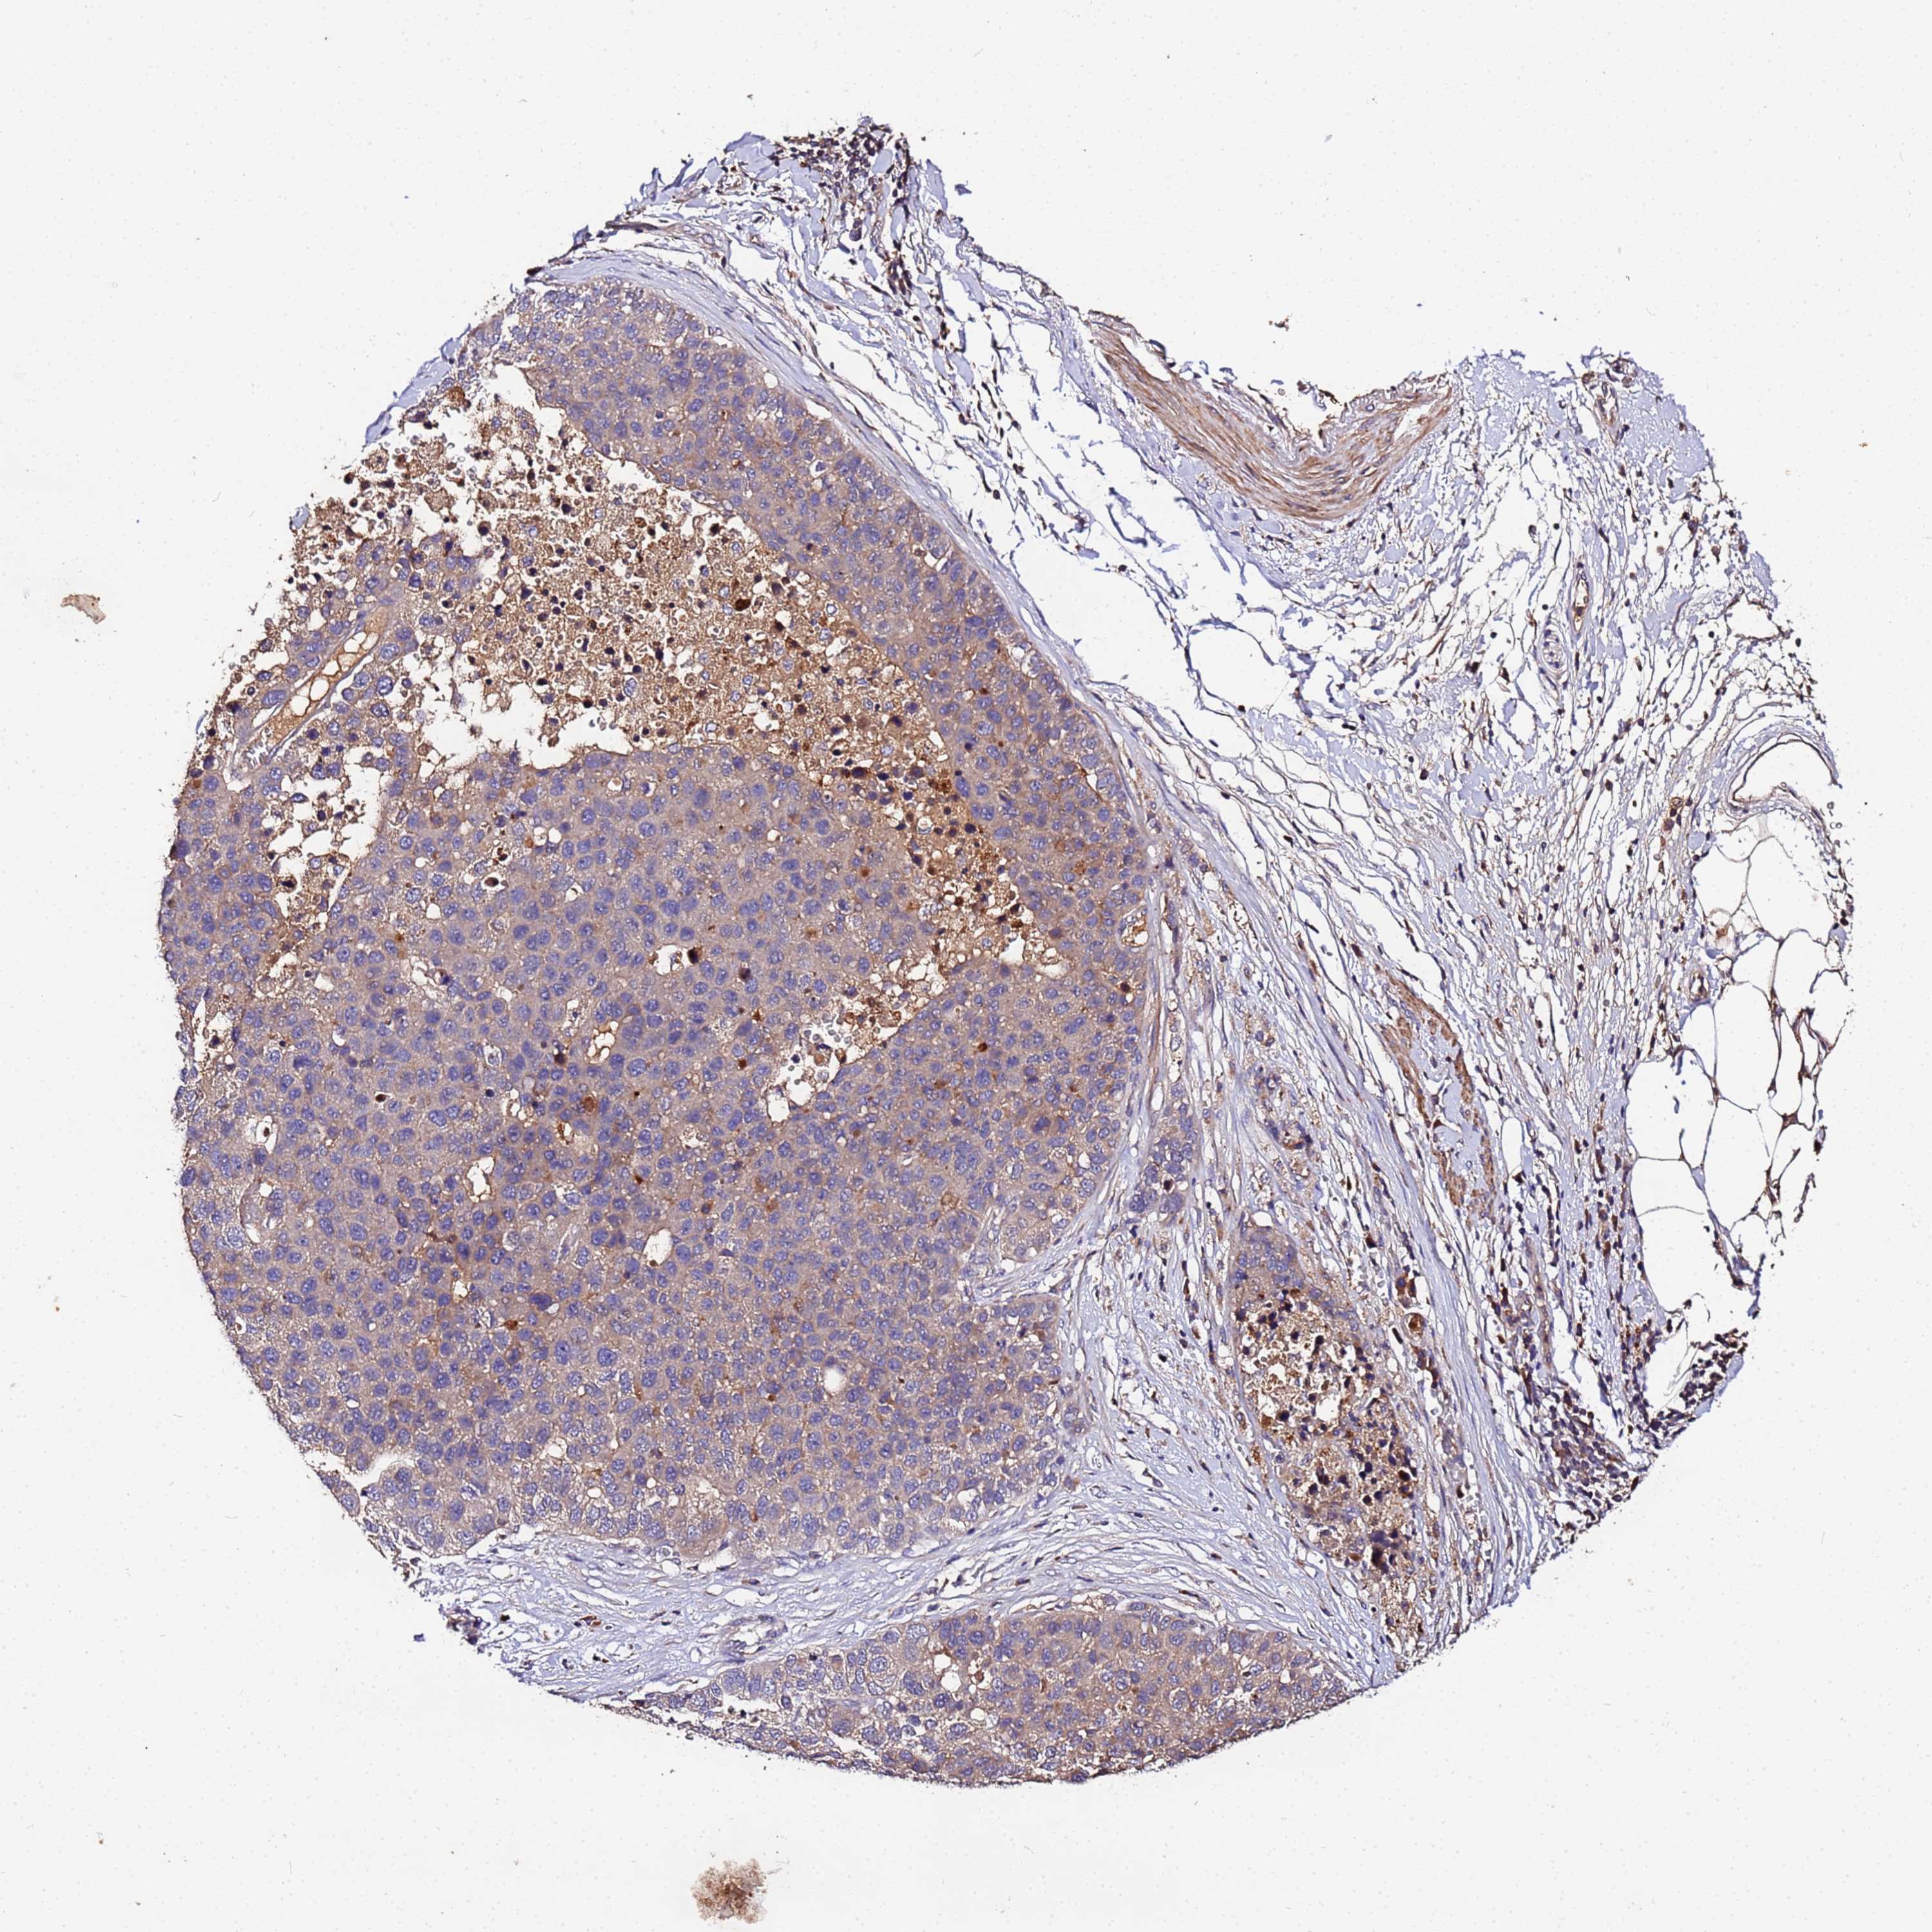

PANCREATIC CANCER - Protein expressioni

A mouse-over function shows sample information and annotation data. Click on an image to view it in a full screen mode. Samples can be filtered based on level of antibody staining by selecting one or several of the following categories: high, medium, low and not detected. The assay and annotation is described here.

Note that samples used for immunohistochemistry by the Human Protein Atlas do not correspond to samples in the TCGA dataset.

Antibody stainingi

Antibody staining in the annotated cell types in the current human tissue is reported as not detected, low, medium, or high, based on conventional immunohistochemistry profiling in selected tissues. This score is based on the combination of the staining intensity and fraction of stained cells.

Each image is clickable and will lead to virtual microscopy that enables deeper exploration of all samples and also displays staining intensity scores, fraction scores and subcellular localization as well as patient and tissue information for each sample.

Antibody HPA044894

Staining

High

Medium

Low

Not detected

Intensity

Strong

Moderate

Weak

Negative

Quantity

>75%

75%-25%

<25%

None

Location

Nuclear

Cytoplasmic/membranous

Cytoplasmic/membranous,nuclear

Adenocarcinoma, NOS